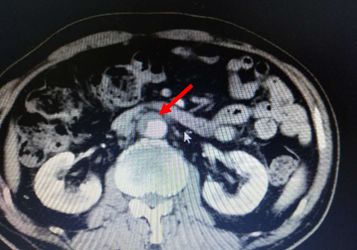

腹部CT检查结果如下:

考虑慢性胰腺炎,脾静脉血栓形成,伴脾门及胃周多发侧枝血管形成,同时合并腹主动脉夹层ⅢB型(Debakey分型),立即严格控制血压在120/80 mmHg一下,同时内科止血、输血后HGB达97 g/L转外科进一步治疗(脾切除术+胃周血管离断术以及腹主动脉支架植入术)。